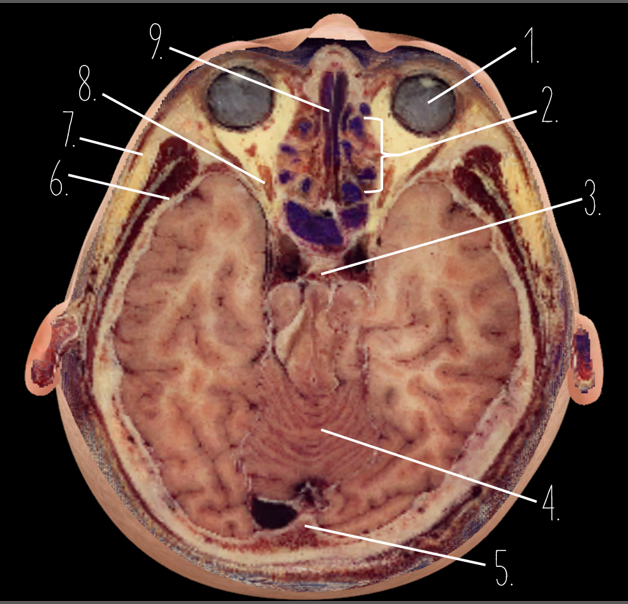

1?

Globe of Eye

2?

Ethmoid Sinus

3?

Pituitary Gland

4?

Cerebellum

5?

Internal Occipital Protuberance

6?

Wing of Sphenoid

7?

Zygomatic Arch

8?

Optic Nerve

9?

Vomer